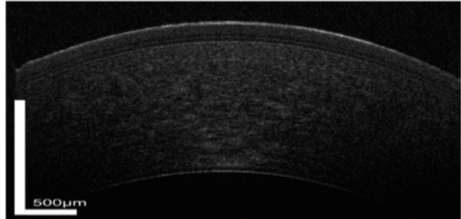

La película lagrimal cubre la córnea y la esclerótica, aunque tiene solo un grosor de algunas μm, su composición es compleja y juega un papel clave en la protección y nutrición de la córnea. Cuando el ojo se mantiene abierto, la película lagrimal se adelgaza con el tiempo hasta que se rompe, lo que requiere un parpadeo para refrescar la superficie ocular (3).

La película lagrimal tiene tres capas distintas: A partir de la superficie más externa, la capa de lípidos que proporciona una barrera hidrofóbica que reduce la tensión superficial y ayuda a volver a extender las lágrimas después de cada parpadeo. La capa acuosa es la parte más gruesa y promueve la difusión de la película lagrimal y la regulación osmótica. Desempeña un papel importante en la oxigenación de la córnea y proporciona el sistema de defensa contra la infección. Por último la capa más interna de mucina que compensa la irregularidad de la córnea, reduce la fricción durante el parpadeo y juega un papel en la eliminación de desechos.

Los abordajes para visualizar alteraciones en pacientes afectación en la película lagrimal utilizando AS OCT se pueden dividir en dos categorías: visualización de las estructuras anatómicas que se ven afectadas por la enfermedad, así como la visualización directa de la película lagrimal (4).